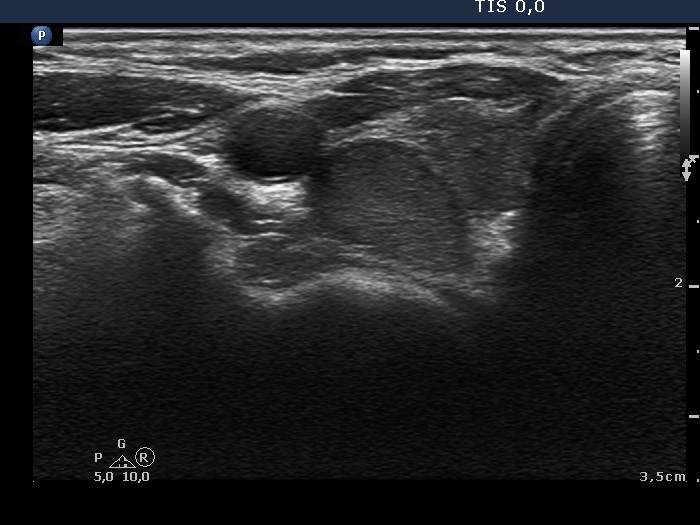

First examination (first row of images):

Clinical presentation: A 50-year-old woman was referred for evaluation of complaints suggesting hypothyroidism.

Palpation: Both lobes were firm.

Laboratory tests: TSH 23.7 mIU/L. Other results including serum calcium and phosphorus were in the normal range.

Ultrasonography: The thyroid was moderately hypoechogenic. There were two more hypoechogenic lesions in the dorsal part of the right lobe.

Aspiration cytology of the lesions in the dorsal part of the thyroid resulted in Hashimoto's thyroiditis.

Daily 75 microgram levothyroxine was given. We advised beside checking the TSH level, a follow-up ultrasound examination 2 years later.